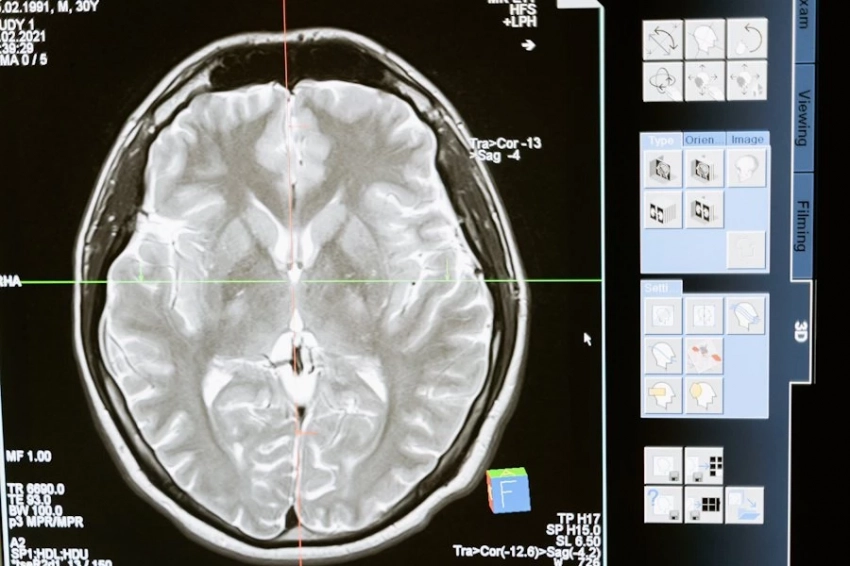

В новой фазе исследования использовались данные от той же группы участников — пожилых людей без признаков деменции. Спустя три года ученые вновь измерили уровень железа в мозге с помощью МРТ, а также проанализировали диетические привычки и когнитивные способности участников.